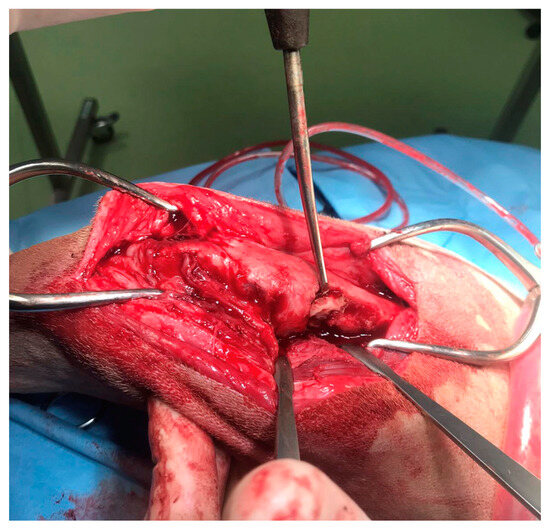

In agreement with the owner, a surgical procedure was performed in order to remove the bone sequestrum, debride necrotic tissues and perform a copious lavage of the affected region (Figure 4). A modified Robert Jones splint was applied for 48 h after the surgery. The patient was hospitalized for 48 h and then discharged with a specific antibiotic therapy (nitrofurantoin 4 mg/kg PO twice daily) and anti-inflammatory therapy (meloxicam 0.1 mg/kg PO once daily). The antibiotic and anti-inflammatory therapy was prescribed and administered to the patient for 30 days once the patient was discharged.

Figure 4. The intraoperative image of the bone sequestrum and the surgical debridement of the necrotic tissue.